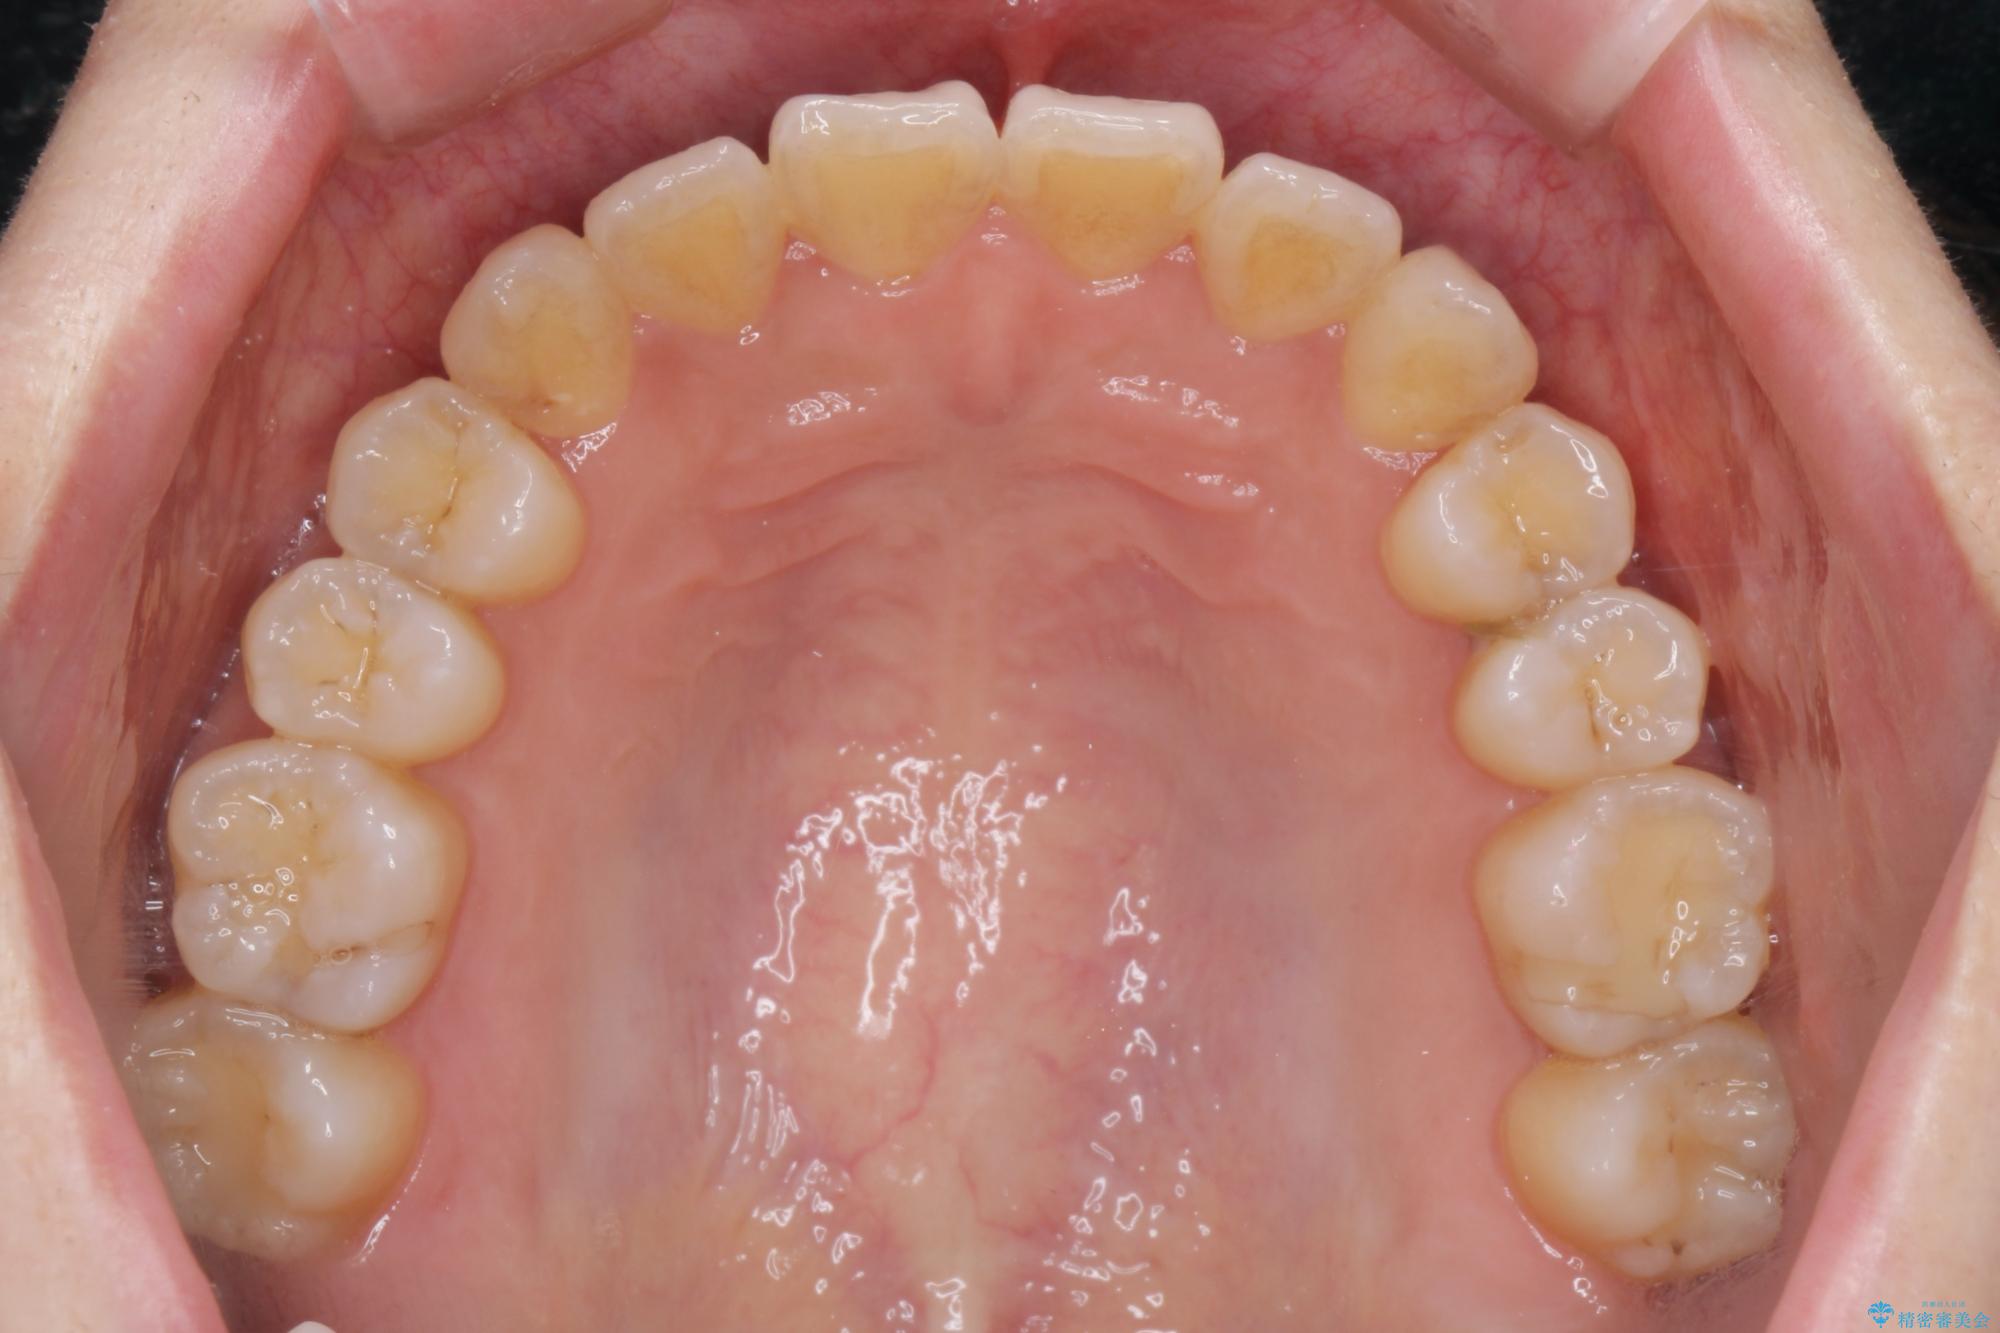

前歯のねじれが気になる、歯並びを改善したいとご来院された患者様です。

歯のねじれをきれいに取るのは、インビザライン(マウスピース矯正)だけでは難しい動きです。そのため、事前に4か月間の部分ワイヤー矯正を行い、治療期間を短くし、より美しい仕上がりを目指す計画です。

前歯が綺麗に並び、大変ご満足いただけました。